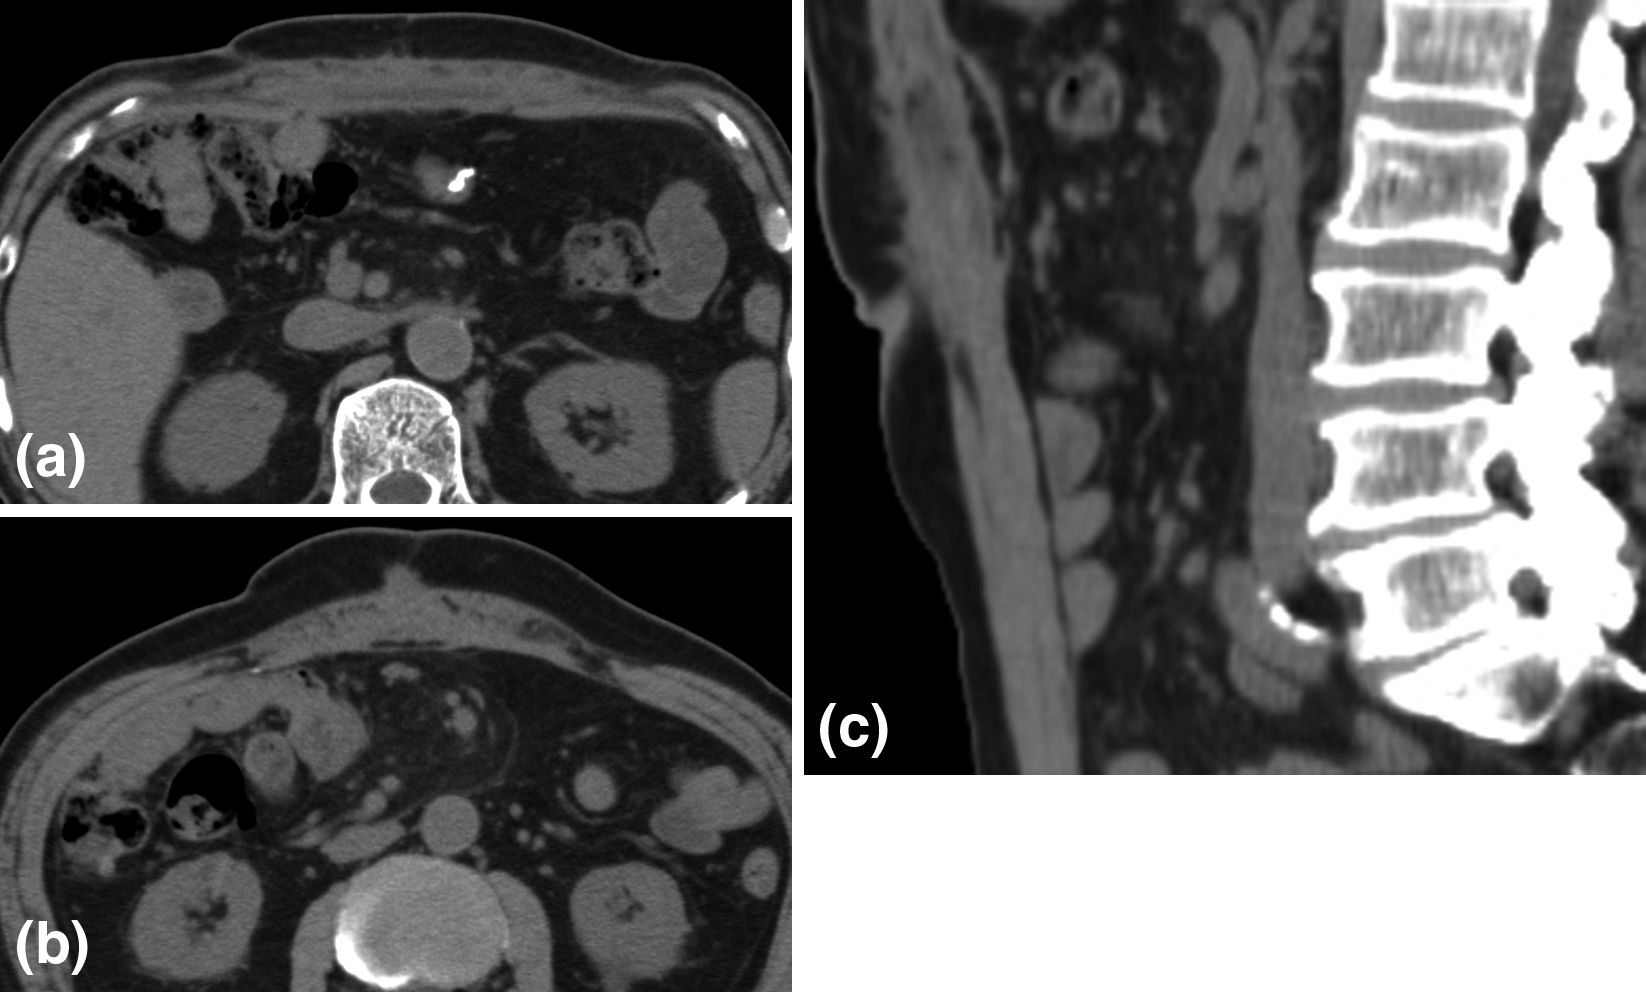

術後経過:術翌日にロキソプロフェンを1錠内服した以外は,周術期を通して全く鎮痛薬を必要としなかった.術後3日目に退院した.術後2週間目に漿液腫を認めたが(Fig. 9),経過観察を行い,術後3か月目には消失した.術後2年が経過したが,再発所見は認めていない(Fig. 10).

CT showed seroma from the epigastric region to the navel at 2 weeks after surgery. (a) (b) axial image. (c) sagittal image.

CT showed no recurrence of incisional hernia at 2 years after surgery. (a) (b) axial image. (c) sagittal image.